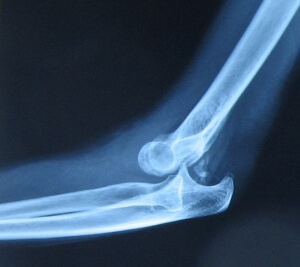

Травматолог назначит рентгенографию, чтобы была возможность правильно поставить диагноз и посмотреть на клиническую картину вывиха локтевого сустава. При таком травмировании назначают ультразвуковое исследование сосудов, чтобы исключить их разрывы и возможные кровотечения.